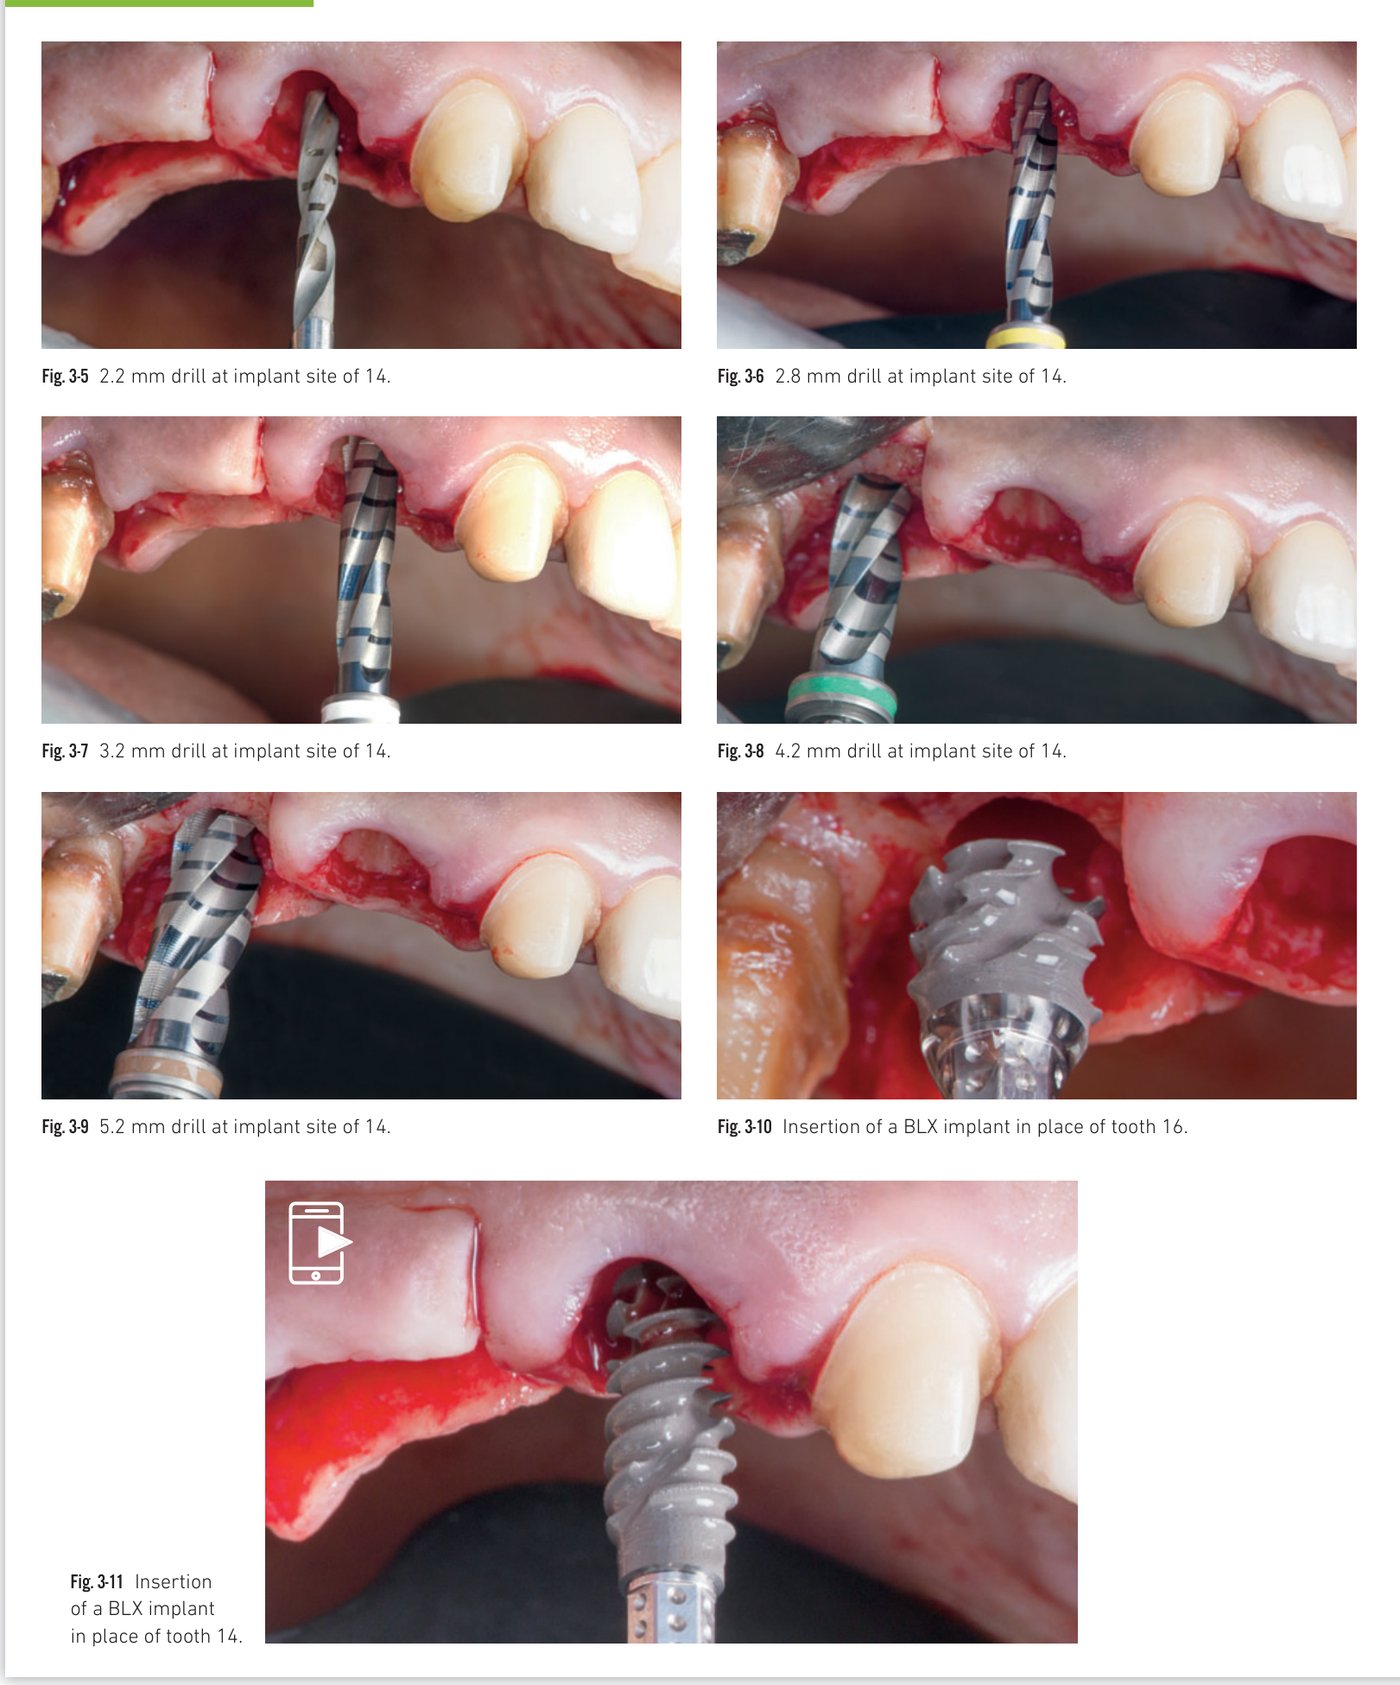

Immediate implant placement in the posterior area

Since an early publication in 1989, immediate implant placement after single-rooted tooth extraction has become a regularly proposed procedure, since successfully extended to multirooted teeth. Cumulative survival rates for implants placed immediately after molar extraction are comparable to those placed in healed sites. The essential factor for success is initial implant stability via apical and/or lateral bone. At a molar extraction site, primary stability may be difficult to achieve due to socket size, poor bone quality, or anatomical limitations (maxillary sinus, mandibular canal). The specific design of the BLX allows satisfactory primary stability even in a very reduced septum.

Clinical situation 2, page 1: Preoperative view, atraumatic extraction, and BLX insertion

Clinical situation 2, page 2: Xenograft filling, collagen sponge, healing, and peri-apical X-ray